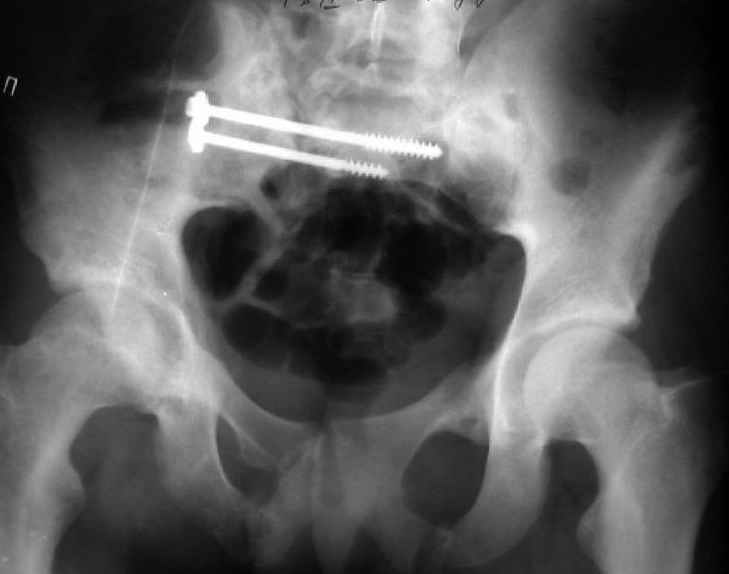

Re: Застарелый перелом таза

Для информации к размышлению о возможности исправления имеющейся деформации предлагаю похожий случай.